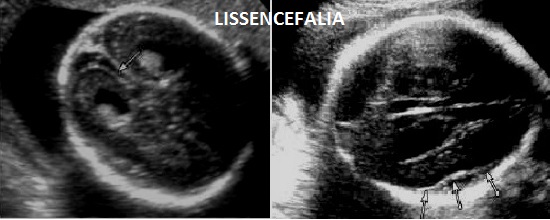

E' un sottotipo di lissencefalia tipo 2 (detta anche "displasia a ciottoli"). Sinonimo è la Sindrome HARD+/- E (idrocefalo, agiria, displasia retinica +/- encefalocele) associata a distrofia muscolare congenita.

La diagnosi ecografica prenatale, non sempre possibile e spesso tardiva, si basa su:idrocefalia, lissencefalia, ipoplasia cerebellare,encefalocele, scoliosi, microftalmia, disgenesia del corpo calloso (lipoma del corpo calloso).

Indicativa per la diagnosi l'associazione presenza di un anello concentrico entro il corpo vitreo, espressione del distacco di retina (non evidenziabile ecograficamente)  e la presenza di lipoma del corpo calloso.

La diagnosi differenziale deve essere principalmente posta con altre anomalie in cui è presente la lissencefalia come la Sindrome di Neu-Laxova e la Sindrome di Miller-Dieker.